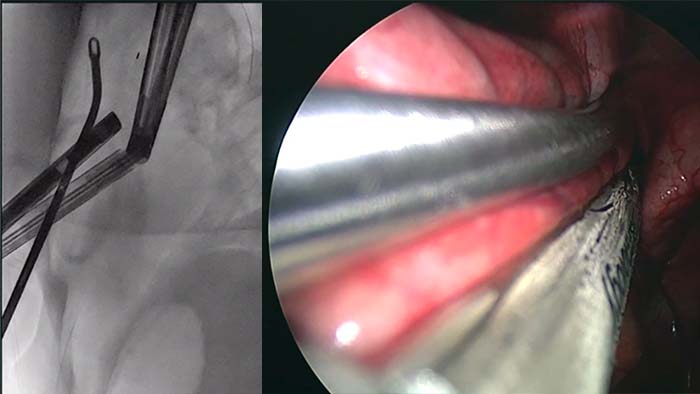

The advanced ceiling-mounted system for cone beam CT bronchoscopy and percutaneous interventions.

The floor-mounted system for cone beam CT bronchoscopy and percutaneous interventions.

Excellent cone beam CT for lung cancer treatments.

Planning and guidance for percutaneous biopsy, marking and ablative therapy.

with tumor segmentation, 3D navigation support for endobronchial procedures.